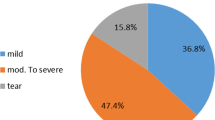

Forty-two patients with history of rotator cuff tear were included in this study. Mean age of the patients was 58.8 ± 7,65 years (range from 40 to 76). Thirteen were female and 29 were male patients. Twenty-eight underwent rotator cuff repair, the time after surgery was 2.3 years (± 0.7). The other patients had a history of rotator cuff tear but were treated conservatively. Patients’ clinical features are shown in Table 1. The maximum diameter of the supraspinatus muscle was detected using conventional ultrasound (b-mode) and this area was marked using a gel capsule (Fig. 3). After detection of this area a shear wave ultra-sound measurement (SWE) of the supraspinatus muscle was performed with a Siemens Acuson S3000 ultrasound system (Siemens AG, Munich, Germany) using a linear transducer (10mHz) the SWV was assessed with the software of the ultrasound device (virtual touch tissue imaging quantification [VTIQ], Siemens Medical Solutions, Siemens AG, Munich, Germany). Tissue elasticity was measured by aligning the transducer parallel to the muscle fibers at the largest diameter of the supraspinatus muscle (Fig. 1). As the process of manually selecting data via the ultrasound system’s console has the potential to significantly introduce bias SWE was performed by one blinded radiologist (DK). The shear wave velocity (m/s) was measured at 10–15 points in the manually placed region of interest in 5 pictures trying to fully cover the muscles cross section. The forearm of the patients was placed on an armrest to avoid muscle contraction during the examination .

All MRIs were rated according the MRI-based Goutallier Classification (oblique-sagittal t1-weighted images) by 5 raters. According to the scaling by Fuchs et al. Grade 0 was defined as no fatty infiltration, grade 1 as some fatty streaking of the supraspinatus, grade 2 as less fat than muscle, grade 3 as equal amounts of fat and muscle, and grade 4 as more fat than muscle [9]. All raters were orthopedic surgeons with clinical focus in shoulder surgery.

Correlation of SWV measured with SWE in the patients’ supraspinatus muscles with the spectroscopic fat ratio showed a Pearson’s ρ of 0.82. This is a good correlation according to the criteria suggested by Landis and Koch [19]. Spectroscopic MRI analysis revealed fat ratios in 42 shoulders ranging from 0 to 77.41%, with a mean FD of 17.9% ± 18.9%. Medians of SWV ranged from 1.59 m/s to 5.32 m/s, with a mean of 1.81 m/s. SWV increased with higher fat water ratio. In four shoulders it was not possible to perform a sufficient SWE, consequently no SWE data were gained for these supraspinatus muscles. In these patients (n = 4) the mean diameter of overlying soft tissue was 20.04 mm (ranged from 11.47 mm to 31.44 mm). For the other patients (n = 38) the mean diameter of overlying soft tissue was 12.98 mm (ranged from 10.01 mm to 14.14 mm). The differences in the diameter did not reach the level of statistical significance.

Correlating the Goutallier scale with the spectroscopic fat measurement revealed a correlation of Pearson’s ρ =0.40 and with the SWV a correlation of ρ =0.48 (Table 2). Interpreted according to the criteria after Landis and Koch this represents a moderate agreement.